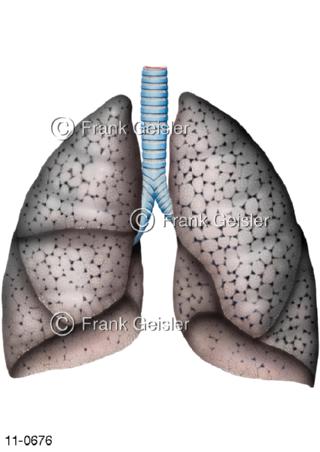

11-0676 Luftröhre Trachea mit Lungen einer Raucherlunge